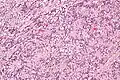

| Micrograph of an intranodal palisaded myofibroblastoma. H&E stain. | |

IPMs are diagnosed by examination of the tissue by a pathologist. They have a rim of peripheral lymphoid tissue (remnant of a lymph node) and consist of spindle cells with nuclear palisading. Red blood cell extravasation is common and blood vessels surrounded by collagen with (fine) peripheral spokes (amianthoid fibers) are usually seen.[2]

Immunostains for smooth muscle actin and cyclin D1 are characteristically positive. The main histologic differential diagnosis is schwannoma.

High mag.